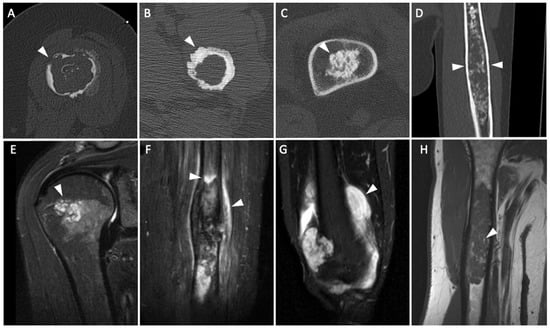

Differentiating Enchondromas and Atypical Cartilaginous Tumors in Long Bones with Computed Tomography and Magnetic Resonance Imaging

3.4. CT and MR Imaging Criteria